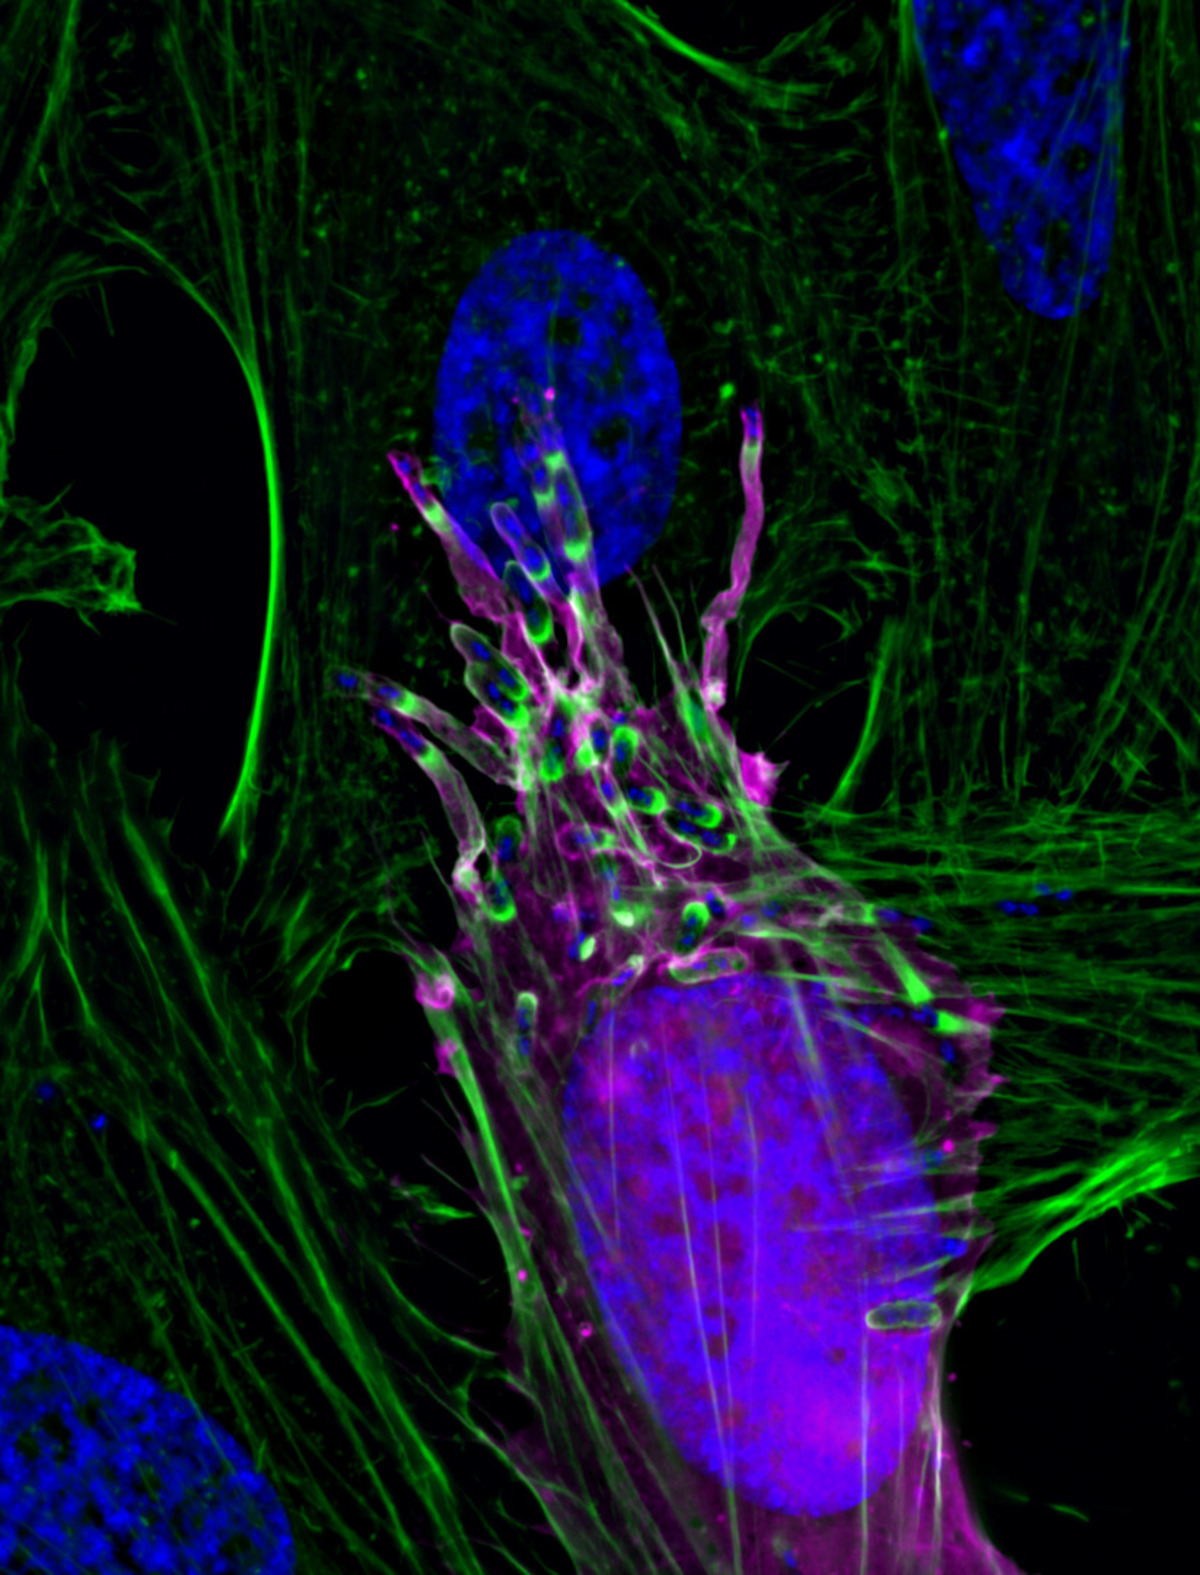

7. Παθογόνα βακτήρια Shigella flexneri

Κάποιος θα μπορούσε να πει ότι η παραπάνω φωτογραφία δείχνει ένα πρόσωπο. Καμία σχέση! Αυτό που απεικονίζει στο μικροσκόπιο ο Δρ. Arandeep S. Dhanda είναι παθογόνα βακτήρια Shigella flexneri που εξαπλώνονται προς τα έξω από ένα μολυσμένο κύτταρο.